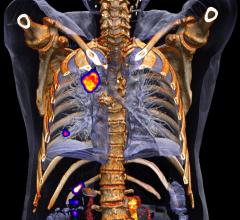

Navidea Biopharmaceuticals Inc. last week announced that the first patient has been enrolled in a clinical study evaluating Lymphoseek (technetium Tc 99m tilmanocept) injection in women with known cervical cancer.

Manhattan Scientifics Inc. announced its wholly-owned subsidiary Senior Scientific LLC, which is developing a platform for the early detection of cancer and other human diseases, has established a research collaboration with Weill Cornell Medicine.